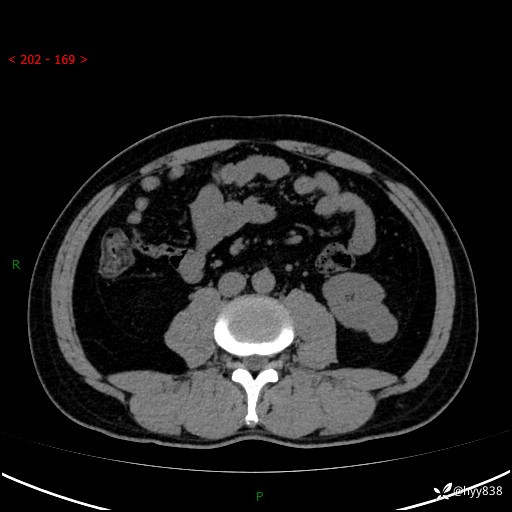

中年男性,左侧腰背部间断性胀痛不适。第一眼“乳头或囊肿”,有无意外---(有结果)

【患者信息】:41岁/男

【主诉】:左侧腰背部间断性胀痛不适1周

【现病史及既往史】:患者1周前无明显诱因出现左侧腰部疼痛,呈间断性胀痛,休息后可缓解,无放射痛,偶可见肉眼血尿,无血块,无尿频尿急尿痛,无夜尿增多,无畏寒发热、咳嗽咳痰等症状。于我院查双肾CT示:左肾占位性病变,左肾下极囊性病变,左肾轻度积水,胆囊多发结石。今为求进一步诊治来我院,门诊以“左肾占位性病变”收治入院。 起病以来,患者精神佳,饮食、睡眠良好,大便正常,小便如上诉,体力体重无明显变化。

【检查】:肾脏CT平扫+增强